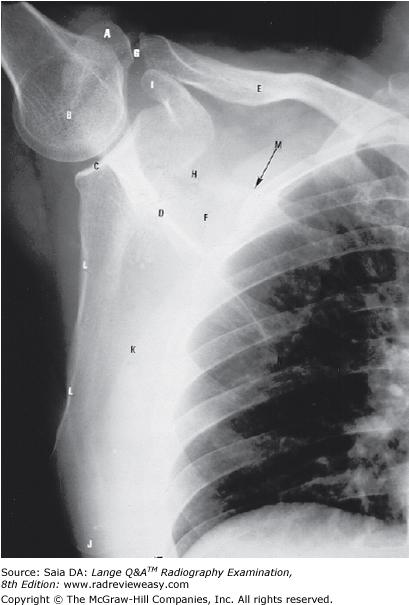

Which of the following statements is (are) true with respect to the radiograph shown in the Figure below?

- The acromion process is seen partially superimposed on the third rib.

- This projection is performed to evaluate the scapula.

- This projection is performed to evaluate the acromioclavicular articulation.

2 only

Which of the following indicates the scapular costal surface seen in the figure below?

K